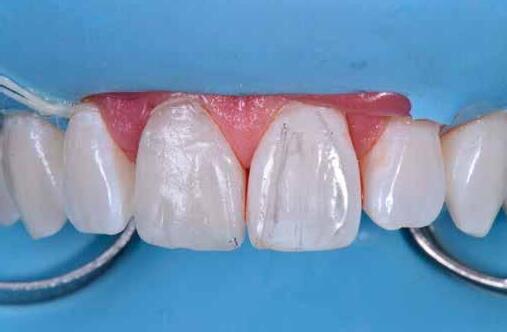

Egy 30 éves, negatív kórtörténettel rendelkező beteg azzal a kéréssel fordult hozzánk, hogy cseréljük ki az UR1 traumája után, 10 évvel korábban készült korábbi kompozit-helyreállítást.

A klinikai vizsgálat során az UR1 reagál a viabilitási tesztre, és az ugyanazon a napon készült röntgenfelvételen nem mutat periapikális elváltozásokat (1. ábra).

Az UR1 elszíneződött, és palatálisabb helyzetben van, mint az ellenoldali központi UL1 (2. ábra)

Az esztétikai elemzés a gingivális zenit aszimmetriáját mutatja az UR1 és az UL1 között. Parodontális szonda segítségével, plexusérzéstelenítés után, az IA

típusú funkcionális hám megváltozott passzív erupcióját igazoljuk Coslet és mtsai. osztályozása szerint (3. ábra)

A lehető legkonzervatívabb helyreállító kezelés elvégzése érdekében a páciensnél, figyelembe véve a megtartott fogelem korát és vitalitását, a tervezés és a diagnosztikai felviaszolás után a közvetlen kompozit-helyreállítás elvégzése mellett döntünk.

A kezelés napján, helyi plexusérzéstelenítést követően, az UR1-et kofferdámmal izoláljuk, kiterjesztve az izolációt az első premolárisokra (4. ábra)

Ezt követően eltávolítjuk a törött kompozt-helyreállítást, és az előkészített fogon rövid ferdére preparálást készítünk, majd az UR1 teljes felületén homokfúvást végzünk 27 μm-es alumínium-oxid porral (5. ábra)

A megváltozott passzív erupció korrigálása érdekében úgy döntöttünk, hogy a fog kiemelkedési profilját a vesztibuláris kidomborodás hangsúlyozásával és az ellenoldali elemmel való szimmetriára törekvéssel újra létrehozzuk. Erre a célra

egy előre megformázott fémmatricát használunk, amelyet két ékkel blokkolunk.

A matrica adaptálása után az adhéziós eljárásokat egy 3 lépéses etch&rinse rendszerrel végezzük. Minden egyes lépést 40 másodperces, UV-fénnyel történő polimerizálás követ (6. ábra)

A vesztibuláris kiemelkedési profilt zománcszínű kompozittal (a TOKUYAMA DENTAL ESTELITE ASTERIA WE termékével) állítjuk helyre (7. ábra).

A diagnosztikai felviaszolás szilikonindexének elkészítése után a palatinális falat zománcszínű kompozittal (a TOKUYAMA DENTAL ESTELITE ASTERIA WE termékével) helyreállítjuk (8. ábra)

Ezt követően helyreállítjuk a dentin anatómiáját a mamelonok reprodukálásával egy átlátszatlan dentinszínű kompozittal (a TOKUYAMA DENTAL ESTELITE SIGMA QUICK OA2 termékével); ez a szín alapvető fontosságú lesz a diszkromatikus elem színének korrigálásához is (9. ábra) Világoskék és fehér hatású árnyalatokat (a TOKUYAMA

DENTAL ESTELITE COLOR termékét) alkalmazunk az opá-

losság emulálásához az incizális területen (10. ábra)

A rétegezést egy zománcszín (a TOKUYAMA DENTAL ESTELITE ASTERIA WE terméke) használatával végezzük a vesztibulárisban, egyszeri hozzáadással. A vesztibuláris felületet háromdimenziós térfogatban modellezzük és vezéreljük annak érdekében, hogy a lehető legkevesebb végső kiigazítás legyen. Ezután 20 másodpercig polimerizáljuk, majd 40 másodpercig polimerizáljuk vesztibulárisan és palatinálisan, miután bevontuk őket gliceringéllel a kompozit hibrid rétegének elkerülése érdekében (11. ábra).

A finírozási és polírozási eljárásokat úgy végezzük, hogy megpróbáljuk emulálni az UL1 átmenő vonalait (12–13. ábra)

A pácienst 21 nap (14–15. ábrák) és 12 hónap (16. ábra) után ismét ellenőrizzük, hogy értékeljük az esztétikai eredményt a forma és a szín tekintetében.